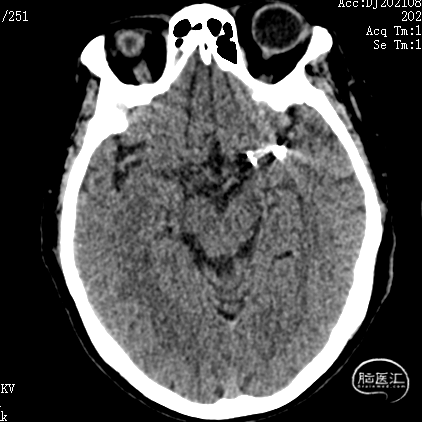

释放支架前经导引导管缓慢注入替罗非班6ml,之后持续静脉泵入,速度5ml/h。手术历时60分钟,麻醉顺利苏醒,神经系统查体:未见阳性体征。NIHSS评分:0分;Raymond分级:Ⅰ级,mRS评分:0分。术后即刻行C-arm CT头颅扫描,未见出血,动脉瘤填塞致密,支架开放良好。

术后3天复查CT示:

1. 双侧基底节区腔隙性脑梗死;

2. 老年性脑改变;

3. 左侧颞叶致密影,考虑术后,请结合临床病史。未见大脑前载瘤动脉远端存在缺血。